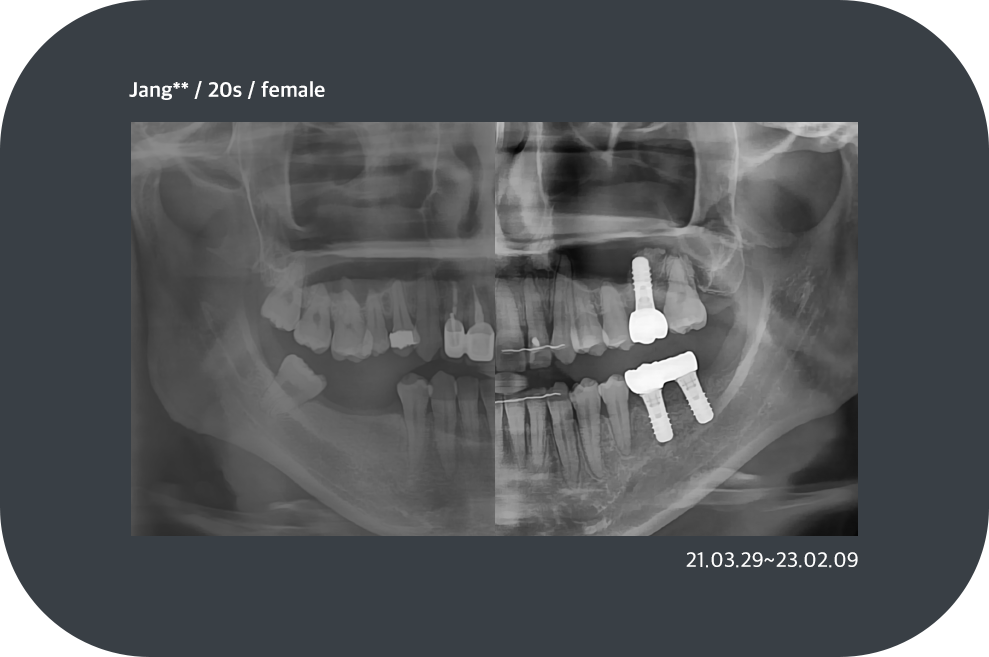

치료사례

임플란트 치료사례

implant_case01

implant_case02

implant_case03

implant_case04

*모든 증례 사진은 의료법 제23조, 제56조에 의거하여, 당사자의 동의하에 게시하였습니다.

*치료 사진은 모두 본원에서 치료한 환자분의 사진입니다.

*치료 사진은 모두 동일인의 사진이며, 동일조건에서 촬영하였습니다.

*개인의 차이에 따라 시술 및 수술 후 부작용이 발생할 수 있으며, 의료진과 충분한 상담을 받으시기 바랍니다.